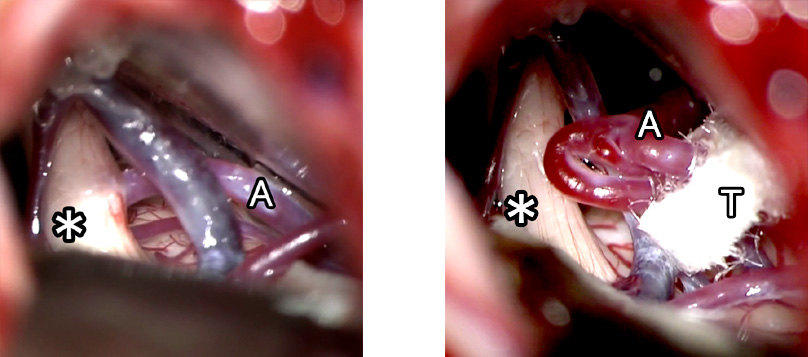

除圧前(左)は血管による圧迫で三叉神経が変形しています。

除圧後(右)はテープによって血管による三叉神経への圧迫がなくなっていることがわかります。

A:血管 *:三叉神経 T:テープ